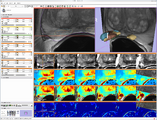

Screenshot of 4D Analysis Module for lung perfusion data. The module provides functionality to analyze time-intensity curves in specified regions.